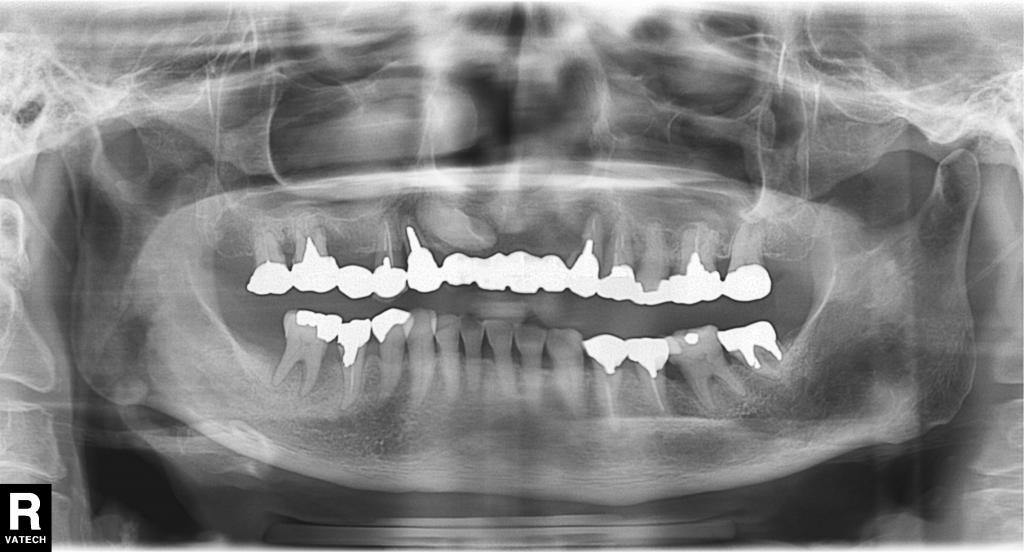

- その時の全体のレントゲン写真です。

前歯も、一部の奥歯も歯の周りの骨が大きく吸収して、動揺している状態でした。